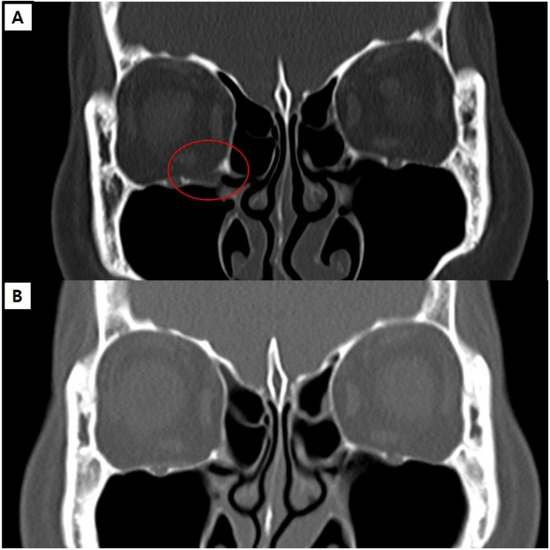

Representative Cases